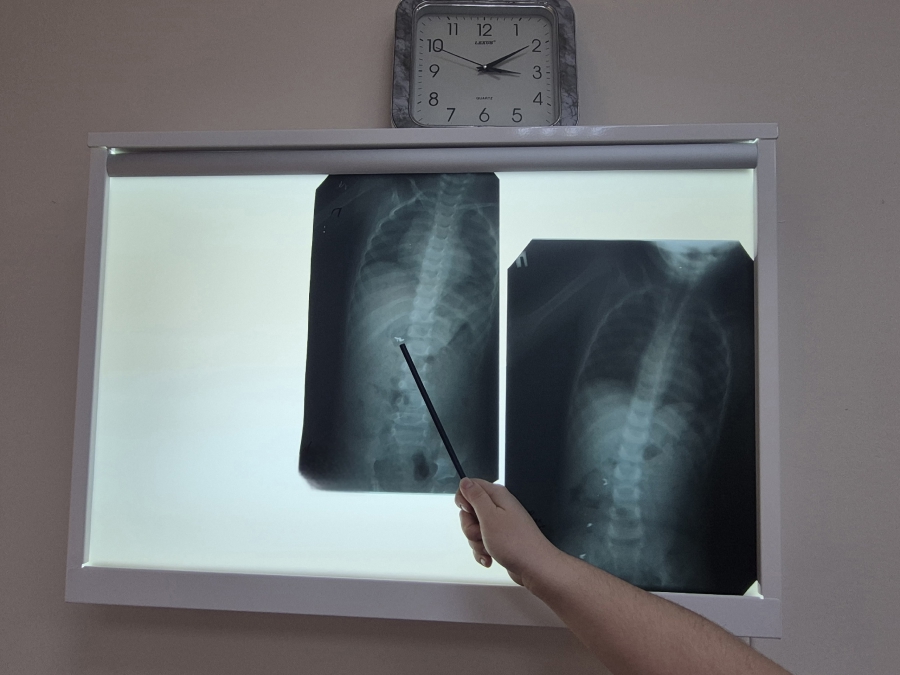

Родители привезли ребенка в Хвалынскую больницу для проведения рентгеновского исследования. Обследование выявило наличие постороннего предмета в желудке маленького пациента. После этого его направили в Балаковскую клиническую больницу (БГКБ) для дальнейшего лечения.

Контрольный рентгеновский снимок показал, что инородное тело состоит из трех частей и что они уже не находятся в желудке, а равномерно распределились по кишечнику.

Также накануне в Балаковскую клиническую больницу госпитализирован 6-летний ребенок, проглотивший десятирублевую монету. Предмет уже ушел блуждать по кишечным петлям. Сейчас несовершеннолетний находится под наблюдением врачей.